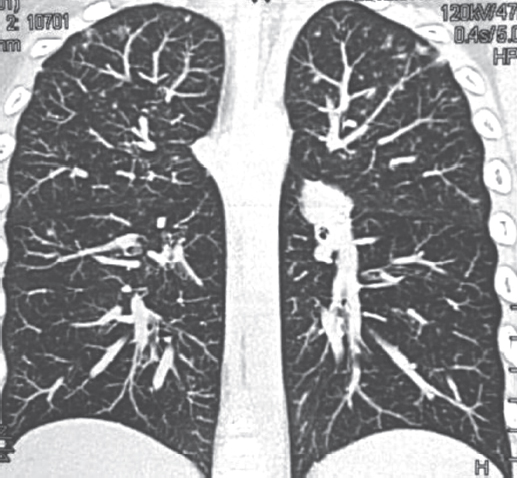

According to scientific research, malignant neoplasms in children are biomedical risk factors for the development of tuberculosis (TB). On the contrary, the occurrence of oncological disease in a child against the background of an existing tuberculous process is extremely rare. The combination of malignant neoplasm and tuberculosis creates difficulties in differential diagnosis, treatment of diseases, prevention of exacerbations and relapses. This article presents a clinical observation – the development of acute lymphoblastic leukemia (ALL) in a 6-year-old child against the background of TB of the intrathoracic lymph nodes during treatment. TB proceeded favorably despite multiple family contact in the child and resistance of Mycobacterium tuberculosis to anti-tuberculosis drugs in adult relatives of the patient. At the onset of ALL, bilateral pulmonary infiltrates and pleural effusion were observed, which were not associated with TB. Specific polychemotherapy for ALL and continued chemotherapy for TB led to the cure of two diseases. Supportive cytostatic and immunosuppressive therapy for ALL required periodic courses of anti-relapse anti-tuberculosis therapy for 5 years. After 10 years of observation, the child is healthy. Thus, the possibility of a rare in clinical practice combination of TB and ALL in children should be taken into account in the diagnosis and treatment of these diseases. During courses of immunosuppressive therapy for ALL, there is a risk of reactivation of TB. It is necessary to recommend long-term observation of such children by a phthisiatrician and an oncologist to prevent recurrence of both diseases.